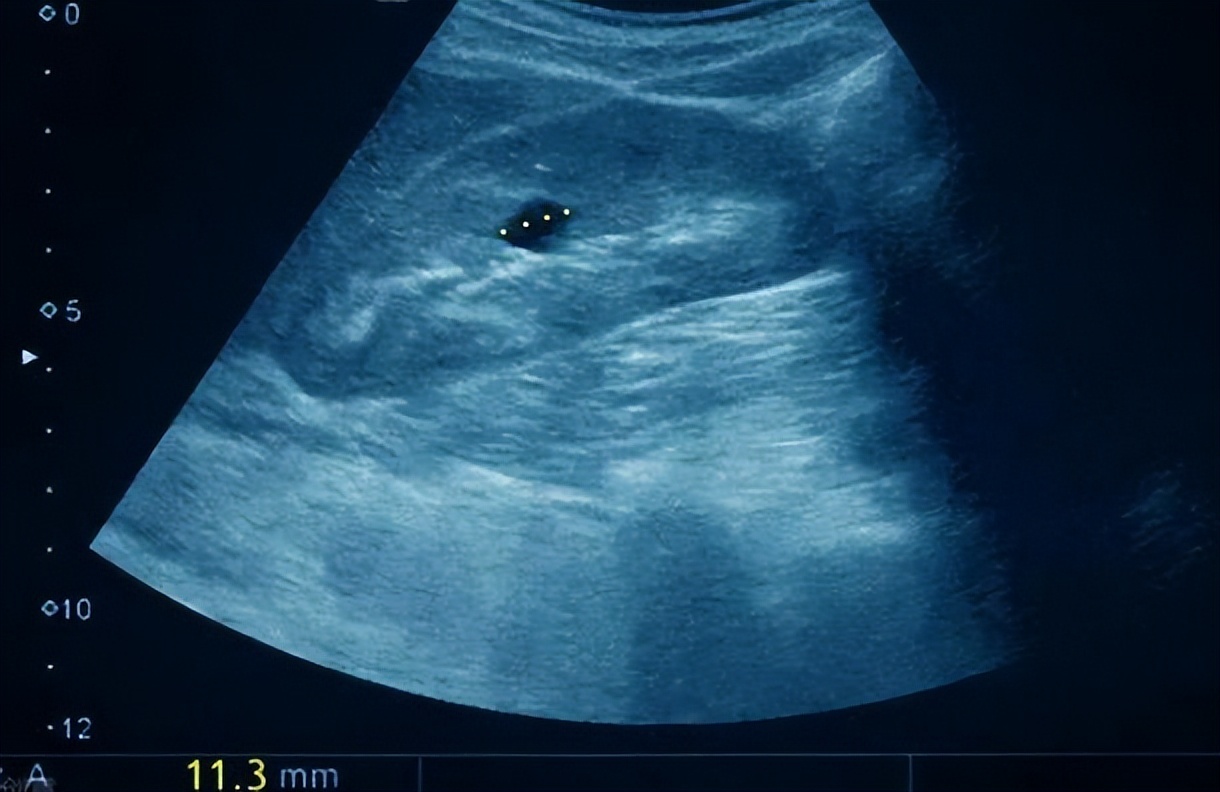

囊肿是一种良性疾病,它可以长在人体表面,也可以长在内脏里;囊肿就是长在体表或体内某一脏器的囊状的良性包块,其内容物的性质是液态的。

囊肿,通常是一种良性的包块。大家可以理解为这是一种长在身体里的“水泡”,它的结构就是外面是一层包膜,包裹着里面的液体。质地比较松软,大多呈半圆形或圆形,大小不一。它可以有很多个,也可以只有单个。